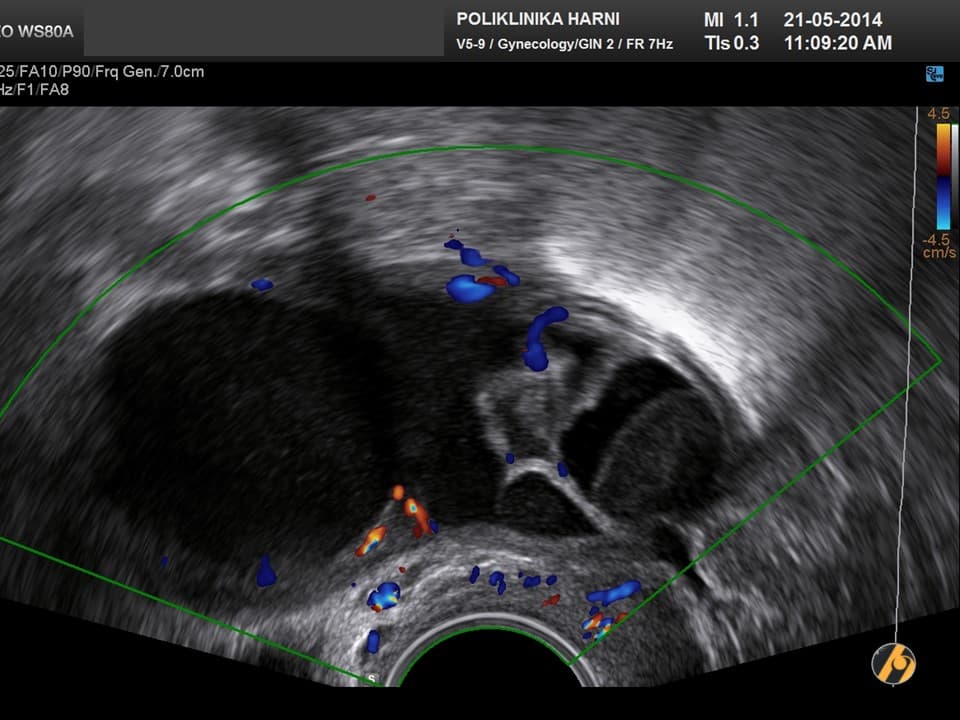

Nažalost, još uvijek ne postoji znanstveno potvrđena dijagnostička metoda koja bi se mogla nazvati metodom probira za karcinom jajnika. Za rano otkriće raka jajnika nužne su i veoma važne redovite ginekološke kontrole uz vaginalni ultrazvuk, odnosno pregled vaginalnim color-Doppler ultrazvukom. U slučaju nejasnih nalaza, uz standardnu laboratorijsku obradu određuju se tumorski biljezi. Optimalni tumorski biljeg za serozne karcinome koji se najčešće javljaju je CA 125, kod rjeđih mucinozni varijanti su to CEA i CA 19-9, a kod endometrioidnih i mucinoznih karcinoma AFP, te ß-hCG kod embrionalnih i koriokarcinoma. U novije vrijeme tumorskim biljezima za rak jajnika su pridodani HE-4 i ROMA indeks.